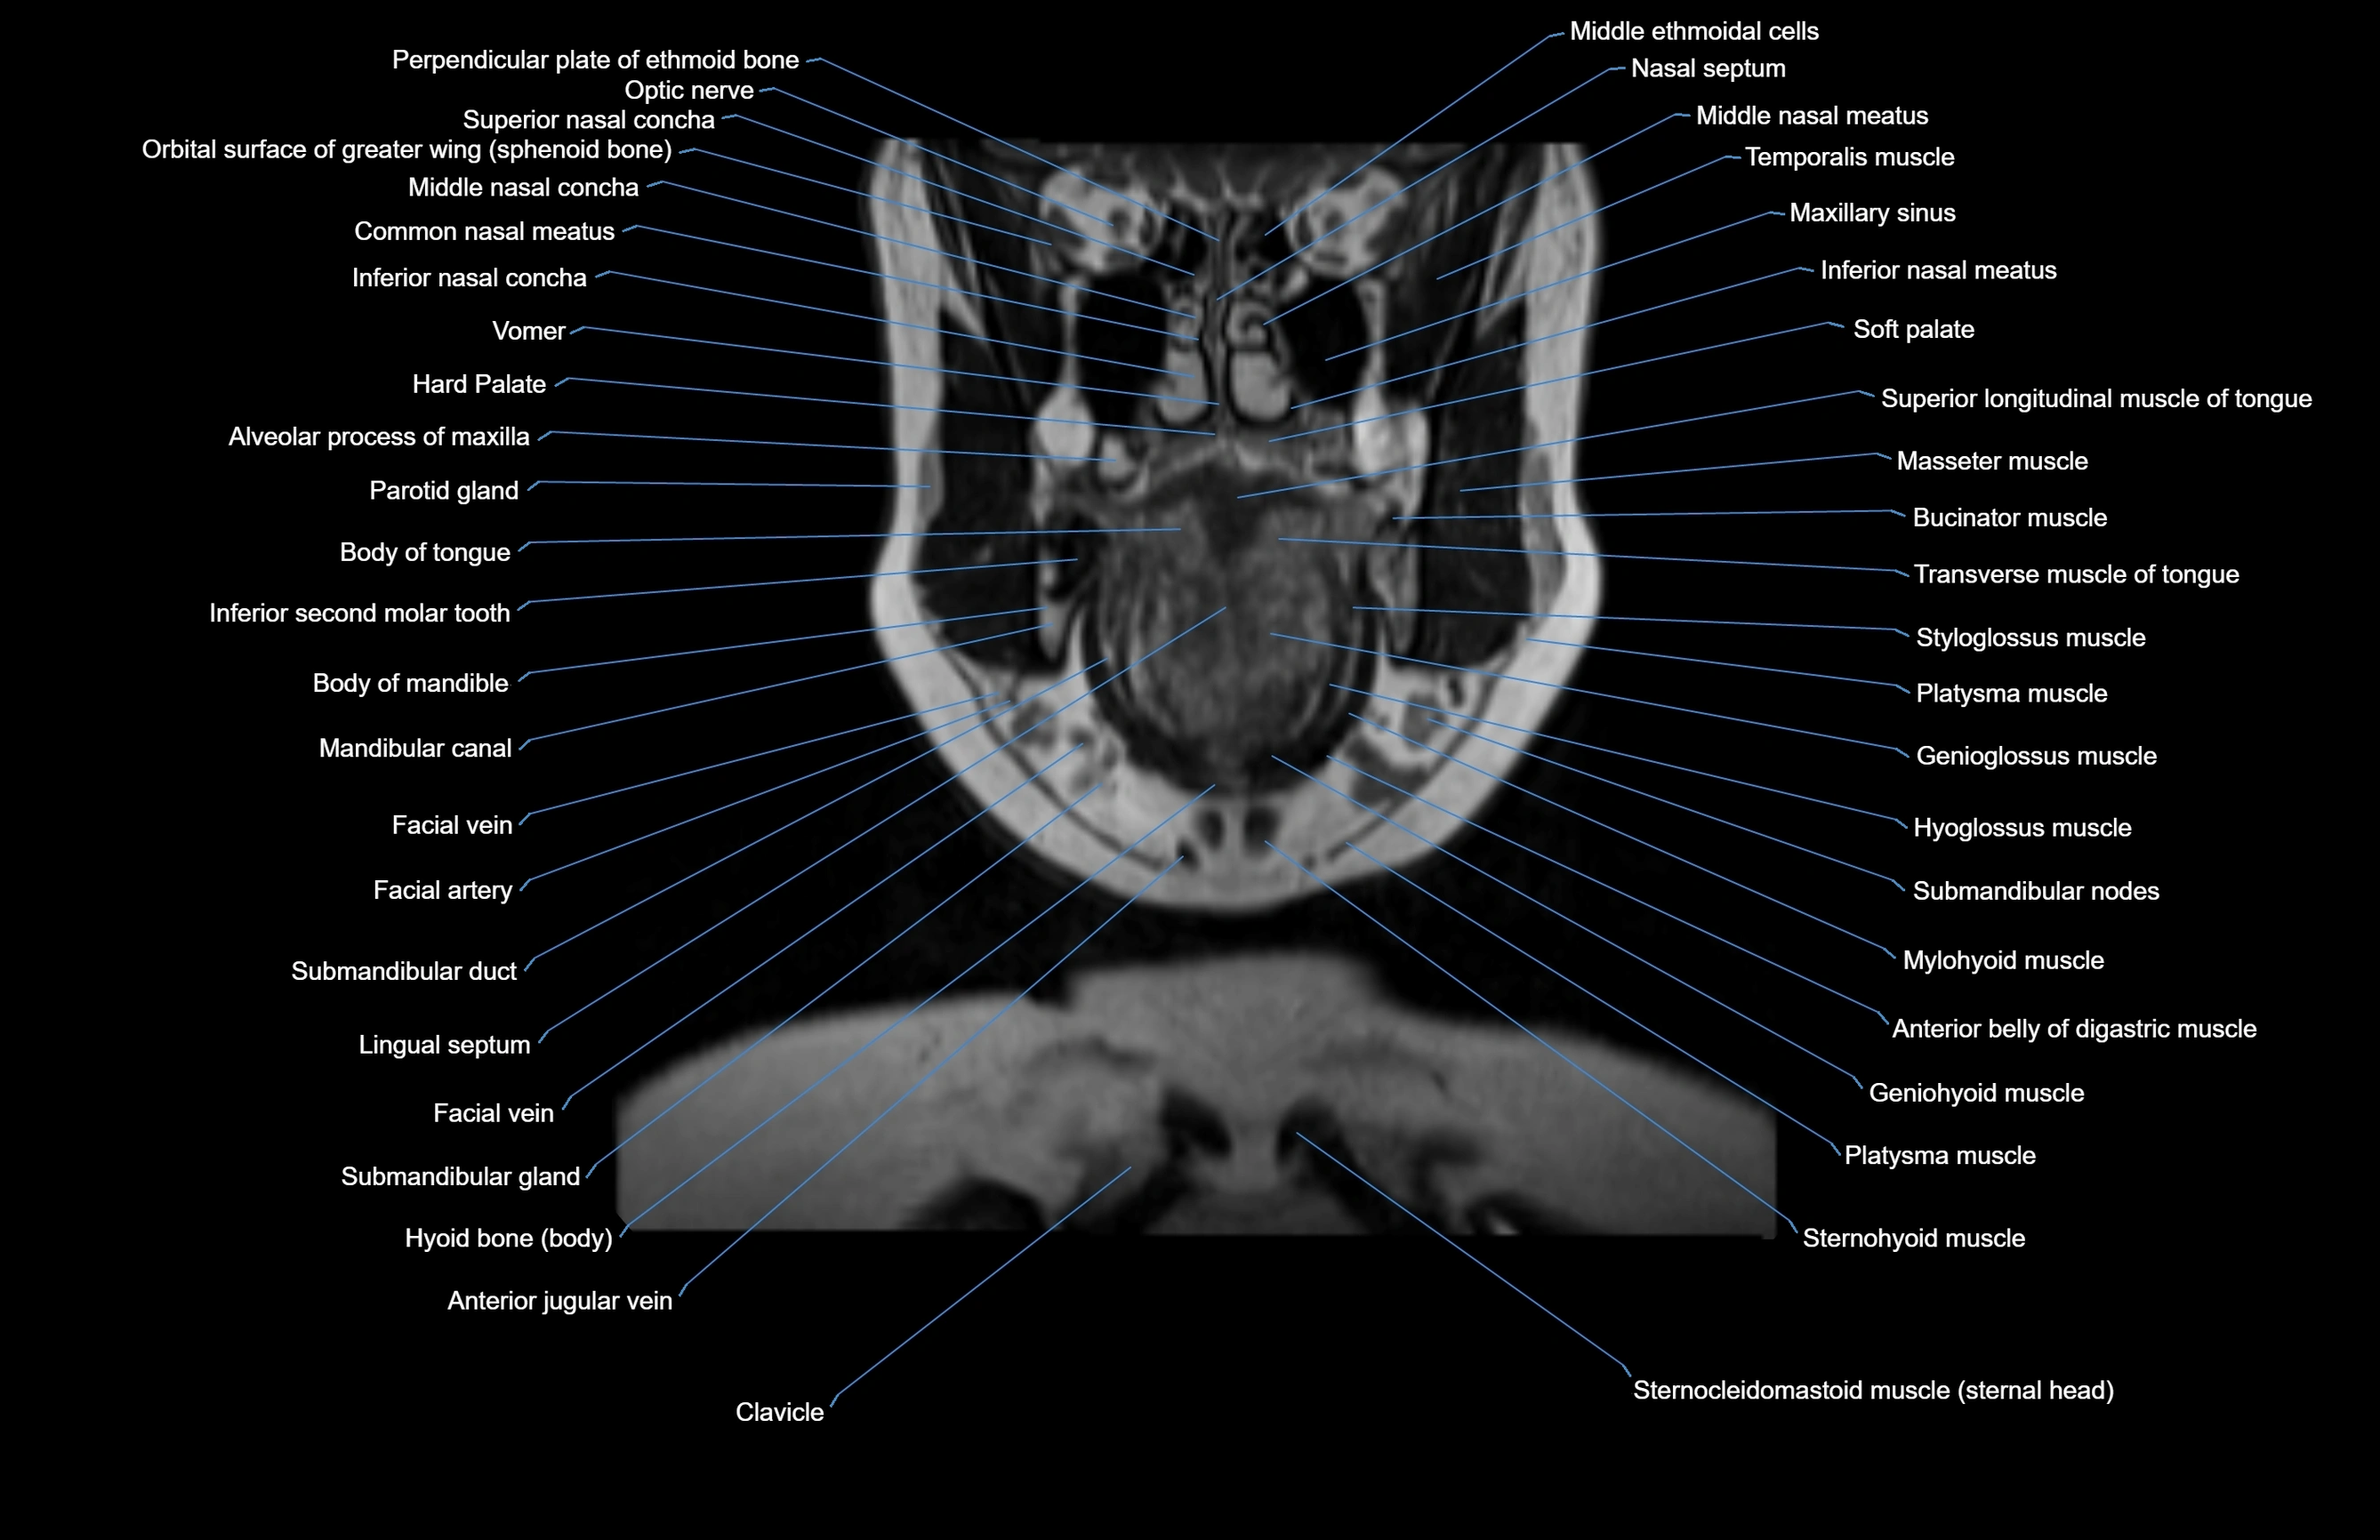

MRI images